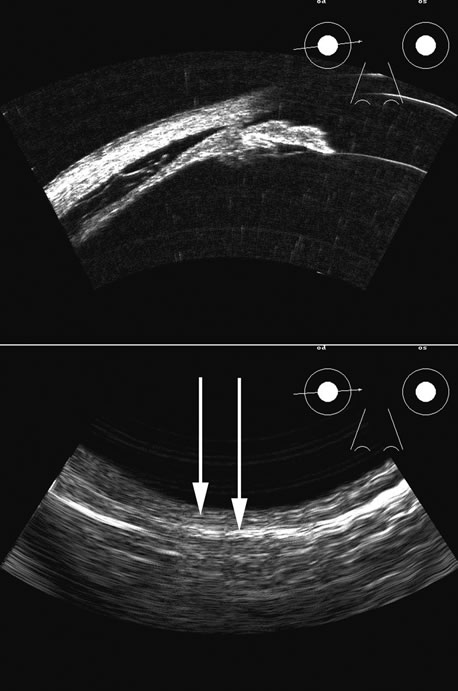

The choroid, like the retina, is highly reflective and may resemble the retina when detached. Its thickness, which includes the retina, Bruch's membrane, and the choriocapillaris (tunica ruyschiana) is not usually differentiable when measured with routine ultrasound;12 however, it may be measured with digital techniques.18 Anatomically, the choroidal elevation is usually a smoothly round, convex surface, limited posteriorly by the vortex veins and anteriorly at any point up to the base of the iris (Fig. 17). The choroidal space should be examined for echoes (blood) or a clear zone, as seen with effusion or the serous part of a hemorrhage. In evaluating membranes from retina or choroid, it is always helpful to repeat the examinations at a later time.

Fig. 17. This patient with a Molteno tube was treated for glaucoma. The top 50 MHz B-scan clearly shows the Molteno Tube (arrow). The bottom 10 MHz B-scan of the same patient demonstrates a choroidal detachment (large arrow) with associated posterior retinal detachment (small arrow). Choroidal elevations are typically convex, highly reflective surfaces with posterior limitation at the vortex vessels. Retina will always attach at the optic nerve. Choroidal elevations are often noted in several quadrants, as seen here.